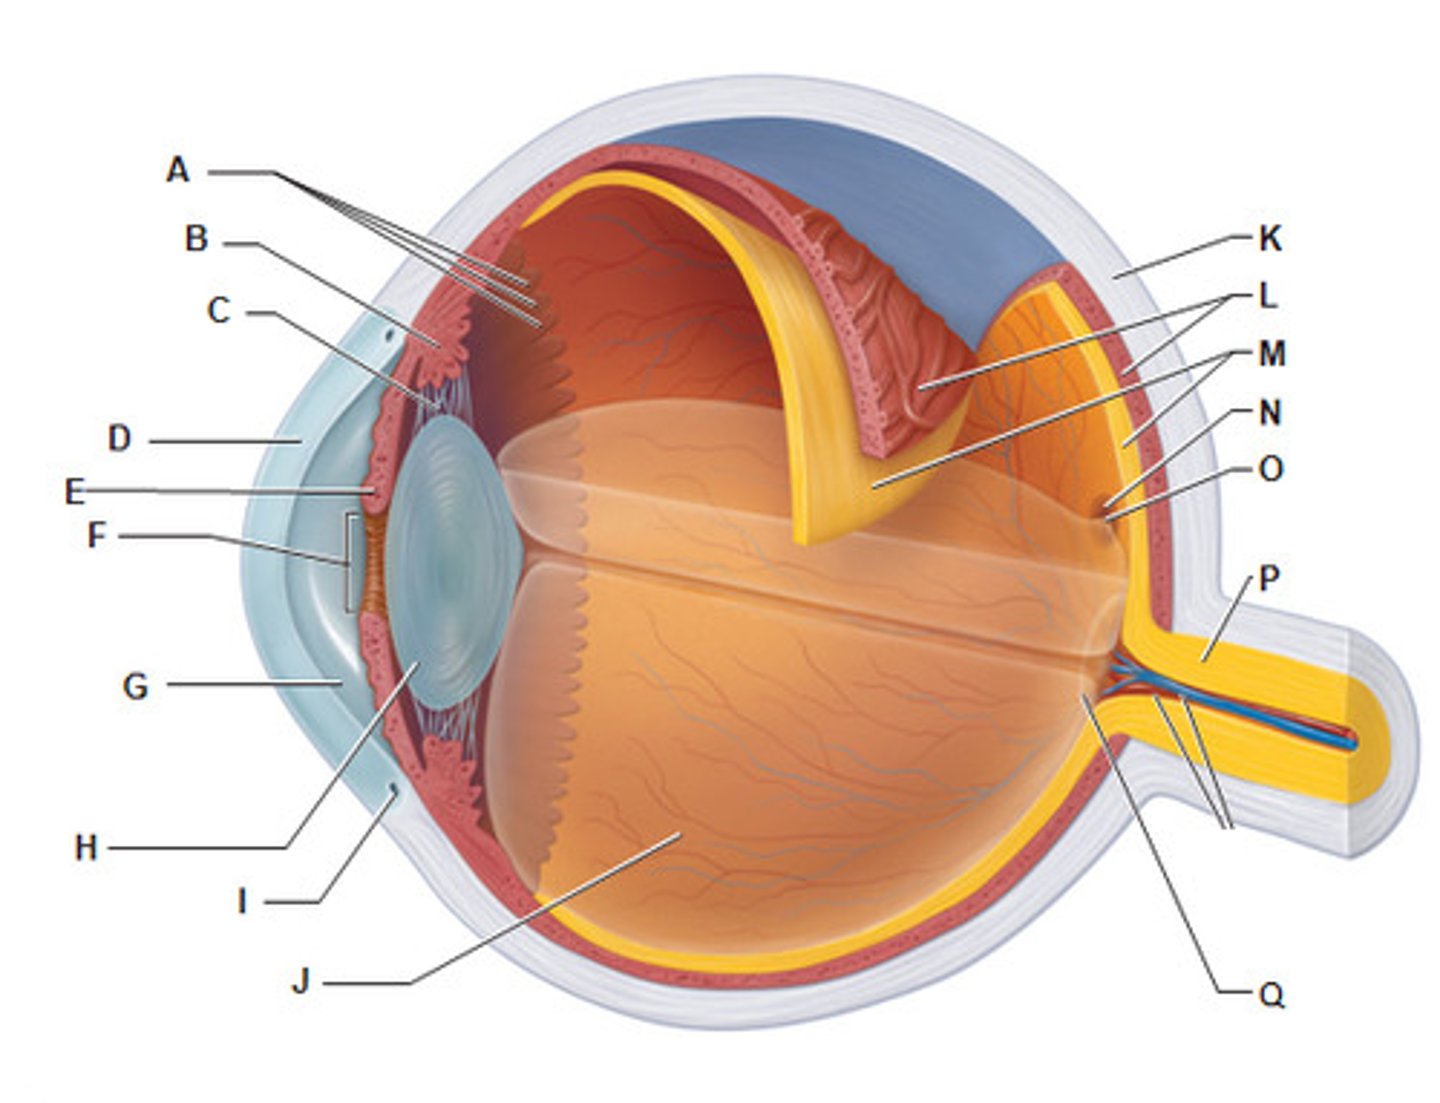

anterior cavity (of eye)

iris

B

optic disk (blind spot)

choroid

L

ciliary body

B

ciliary process

conjunctiva

cornea

D

fovea centralis

suspensory ligaments

C

vitreous humor

lens

H

macula lutea

nasolacrimal duct

lacrimal gland

posterior cavity (of eye)

pupil

F

retina

M

sclera

optic nerve